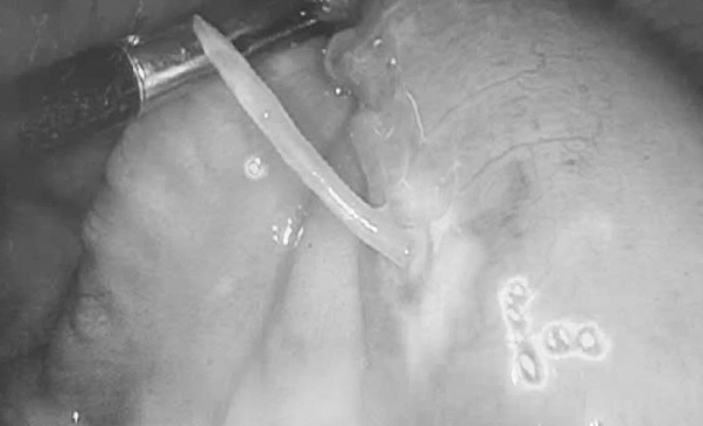

Kết quả chụp CT cho thấy có dị vật xuyên thành ruột non vùng tiểu khung lệch phải. Các bác sĩ Khoa Ngoại tổng hợp - Liên chuyên khoa ngay lập tức chỉ định phẫu thuật lấy dị vật và khâu thủng lỗ ruột non cho người bệnh.